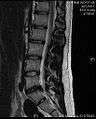

MRI scan of large herniation (on the right) of the disc between the L4-L5 vertebrae.

The majority of spinal disc herniation cases occur in lumbar region (95% in L4-L5 or L5-S1).[22] The second most common site is the cervical region (C5-C6, C6-C7). The thoracic region accounts for only 0.15% to 4.0% of cases. Herniations usually occur posterolaterally, where the anulus fibrosus is relatively thin and is not reinforced by the posterior or anterior longitudinal ligament.[22] In the cervical spinal cord, a symptomatic posterolateral herniation between two vertebrae will impinge on the nerve which exits the spinal canal between those two vertebrae on that side.[22] So for example, a right posterolateral herniation of the disc between vertebrae C5 and C6 will impinge on the right C6 spinal nerve. The rest of the spinal cord, however, is oriented differently, so a symptomatic posterolateral herniation between two vertebrae will actually impinge on the nerve exiting at the next intervertebral foramen down.[22] So for example, a herniation of the disc between the L5 and S1 vertebrae will impinge on the S1 spinal nerve, which exits between the S1 and S2 vertebrae.

- Magnetic resonance imaging (MRI): A diagnostic test that produces three-dimensional images of body structures using powerful magnets and computer technology. It can show the spinal cord, nerve roots, and surrounding areas, as well as enlargement, degeneration, and tumors. It shows soft tissues even better than CAT scans. An MRI performed with a high magnetic field strength usually provides the most conclusive evidence for diagnosis of a disc herniation. T2-weighted images allow for clear visualization of protruded disc material in the spinal canal.